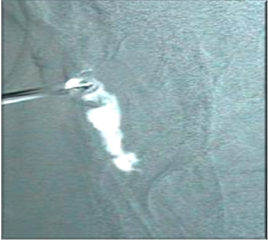

![]() |

| Dacriocystography. Contrast in white is appreciated with a stop region observed |